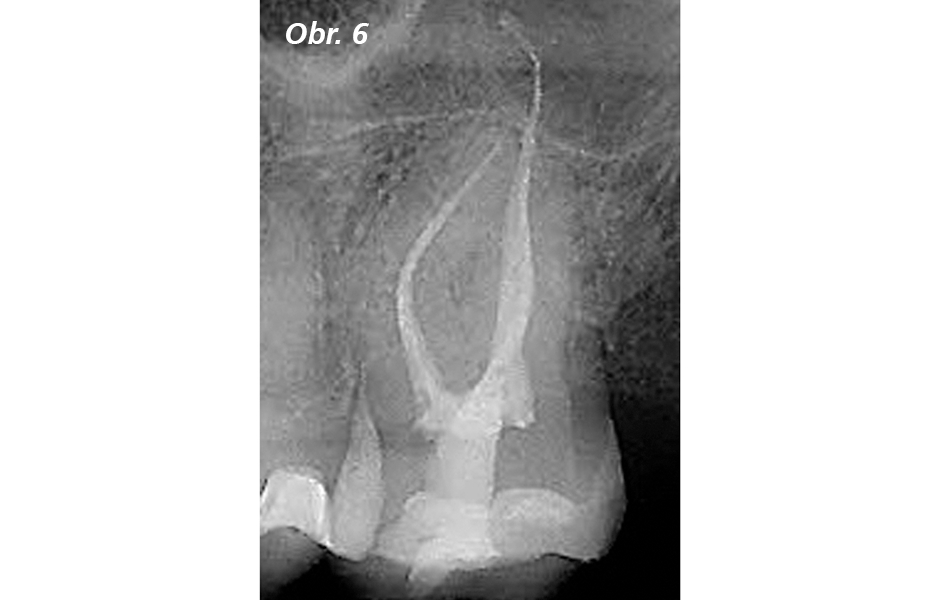

Případy zachycené na obrázcích 4 až 10 – většinou pořízené členy IBAC – mi dělají velkou radost a současně mi navodily počáteční šok: Co to sakra dělají? Malé, tenké vstupy, zachovávající strop dřeňové dutiny intaktní, postranní rohy dřeně nezakryté, nebo celé ošetření kořenových kanálků jen skrze předem vybroušené kavity!

Dolní molár s téměř úplnou kalcifikací dřeňové dutiny před ošetřením kořenových kanálků, provedeným skrz dva dokonale vymezené přístupové vstupní otvory, zanechávající 0,75 mm vysokou úžinu mezi dřeňovou dutinou. Všimněte si konečných výsledků ošetření v